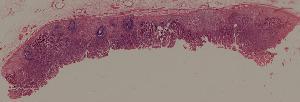

50. Labar pneumonia

51. Carnification of the lung

52. Lobular pneumonia

57. Carcinoma of the lung